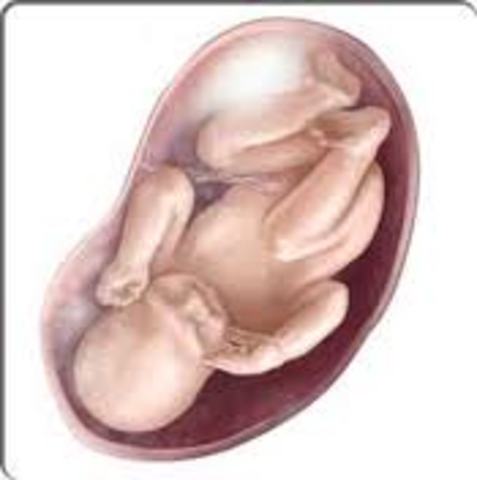

Coming down to the wire, your baby weighs around seven to eight pounds and measures 19 to 21 inches. Those measurements won't change much from now on, but her brain is still growing at an astonishing rate, a pace that will continue for the first three years of life.